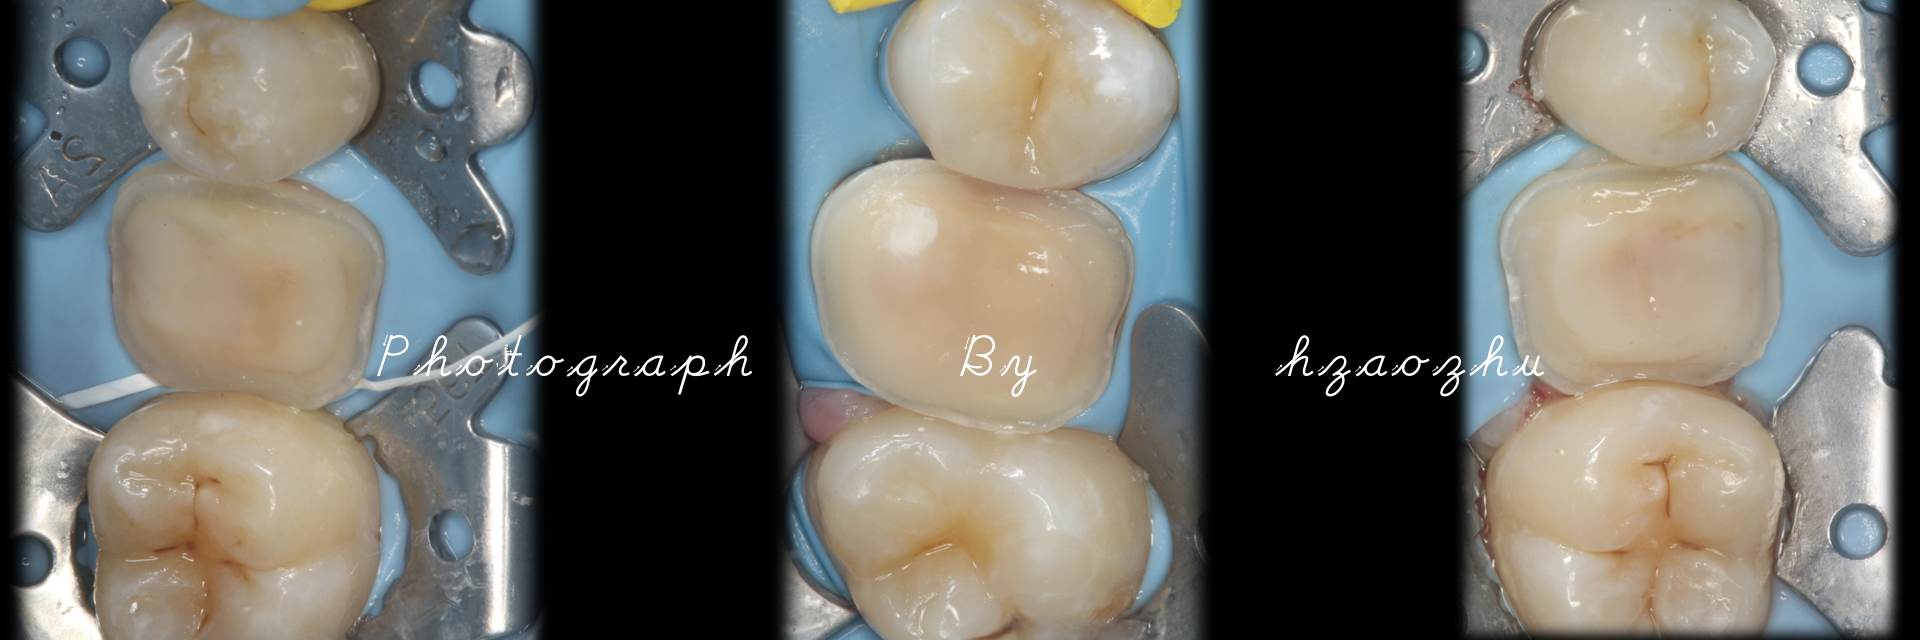

嵌体|E.Max .16.36.46

温州佳洁口腔 朱照鸿 医生 | 技师:尹群